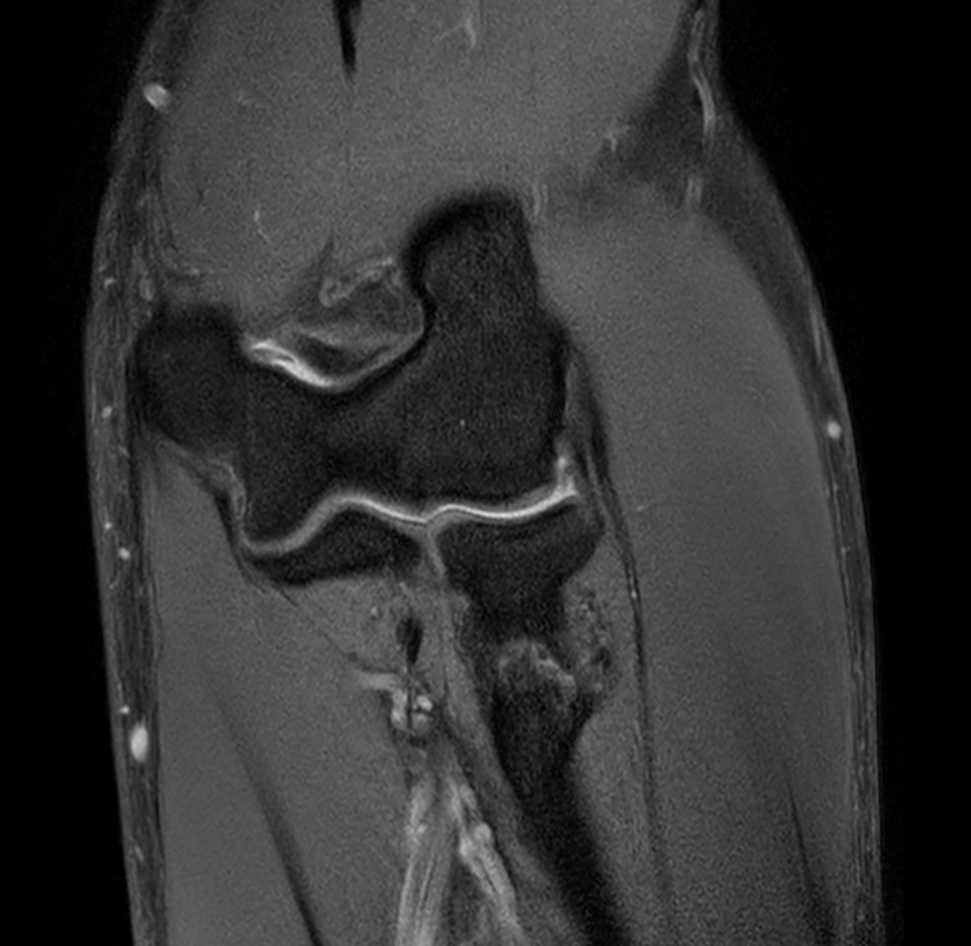

Sagittal PDw SPAIR